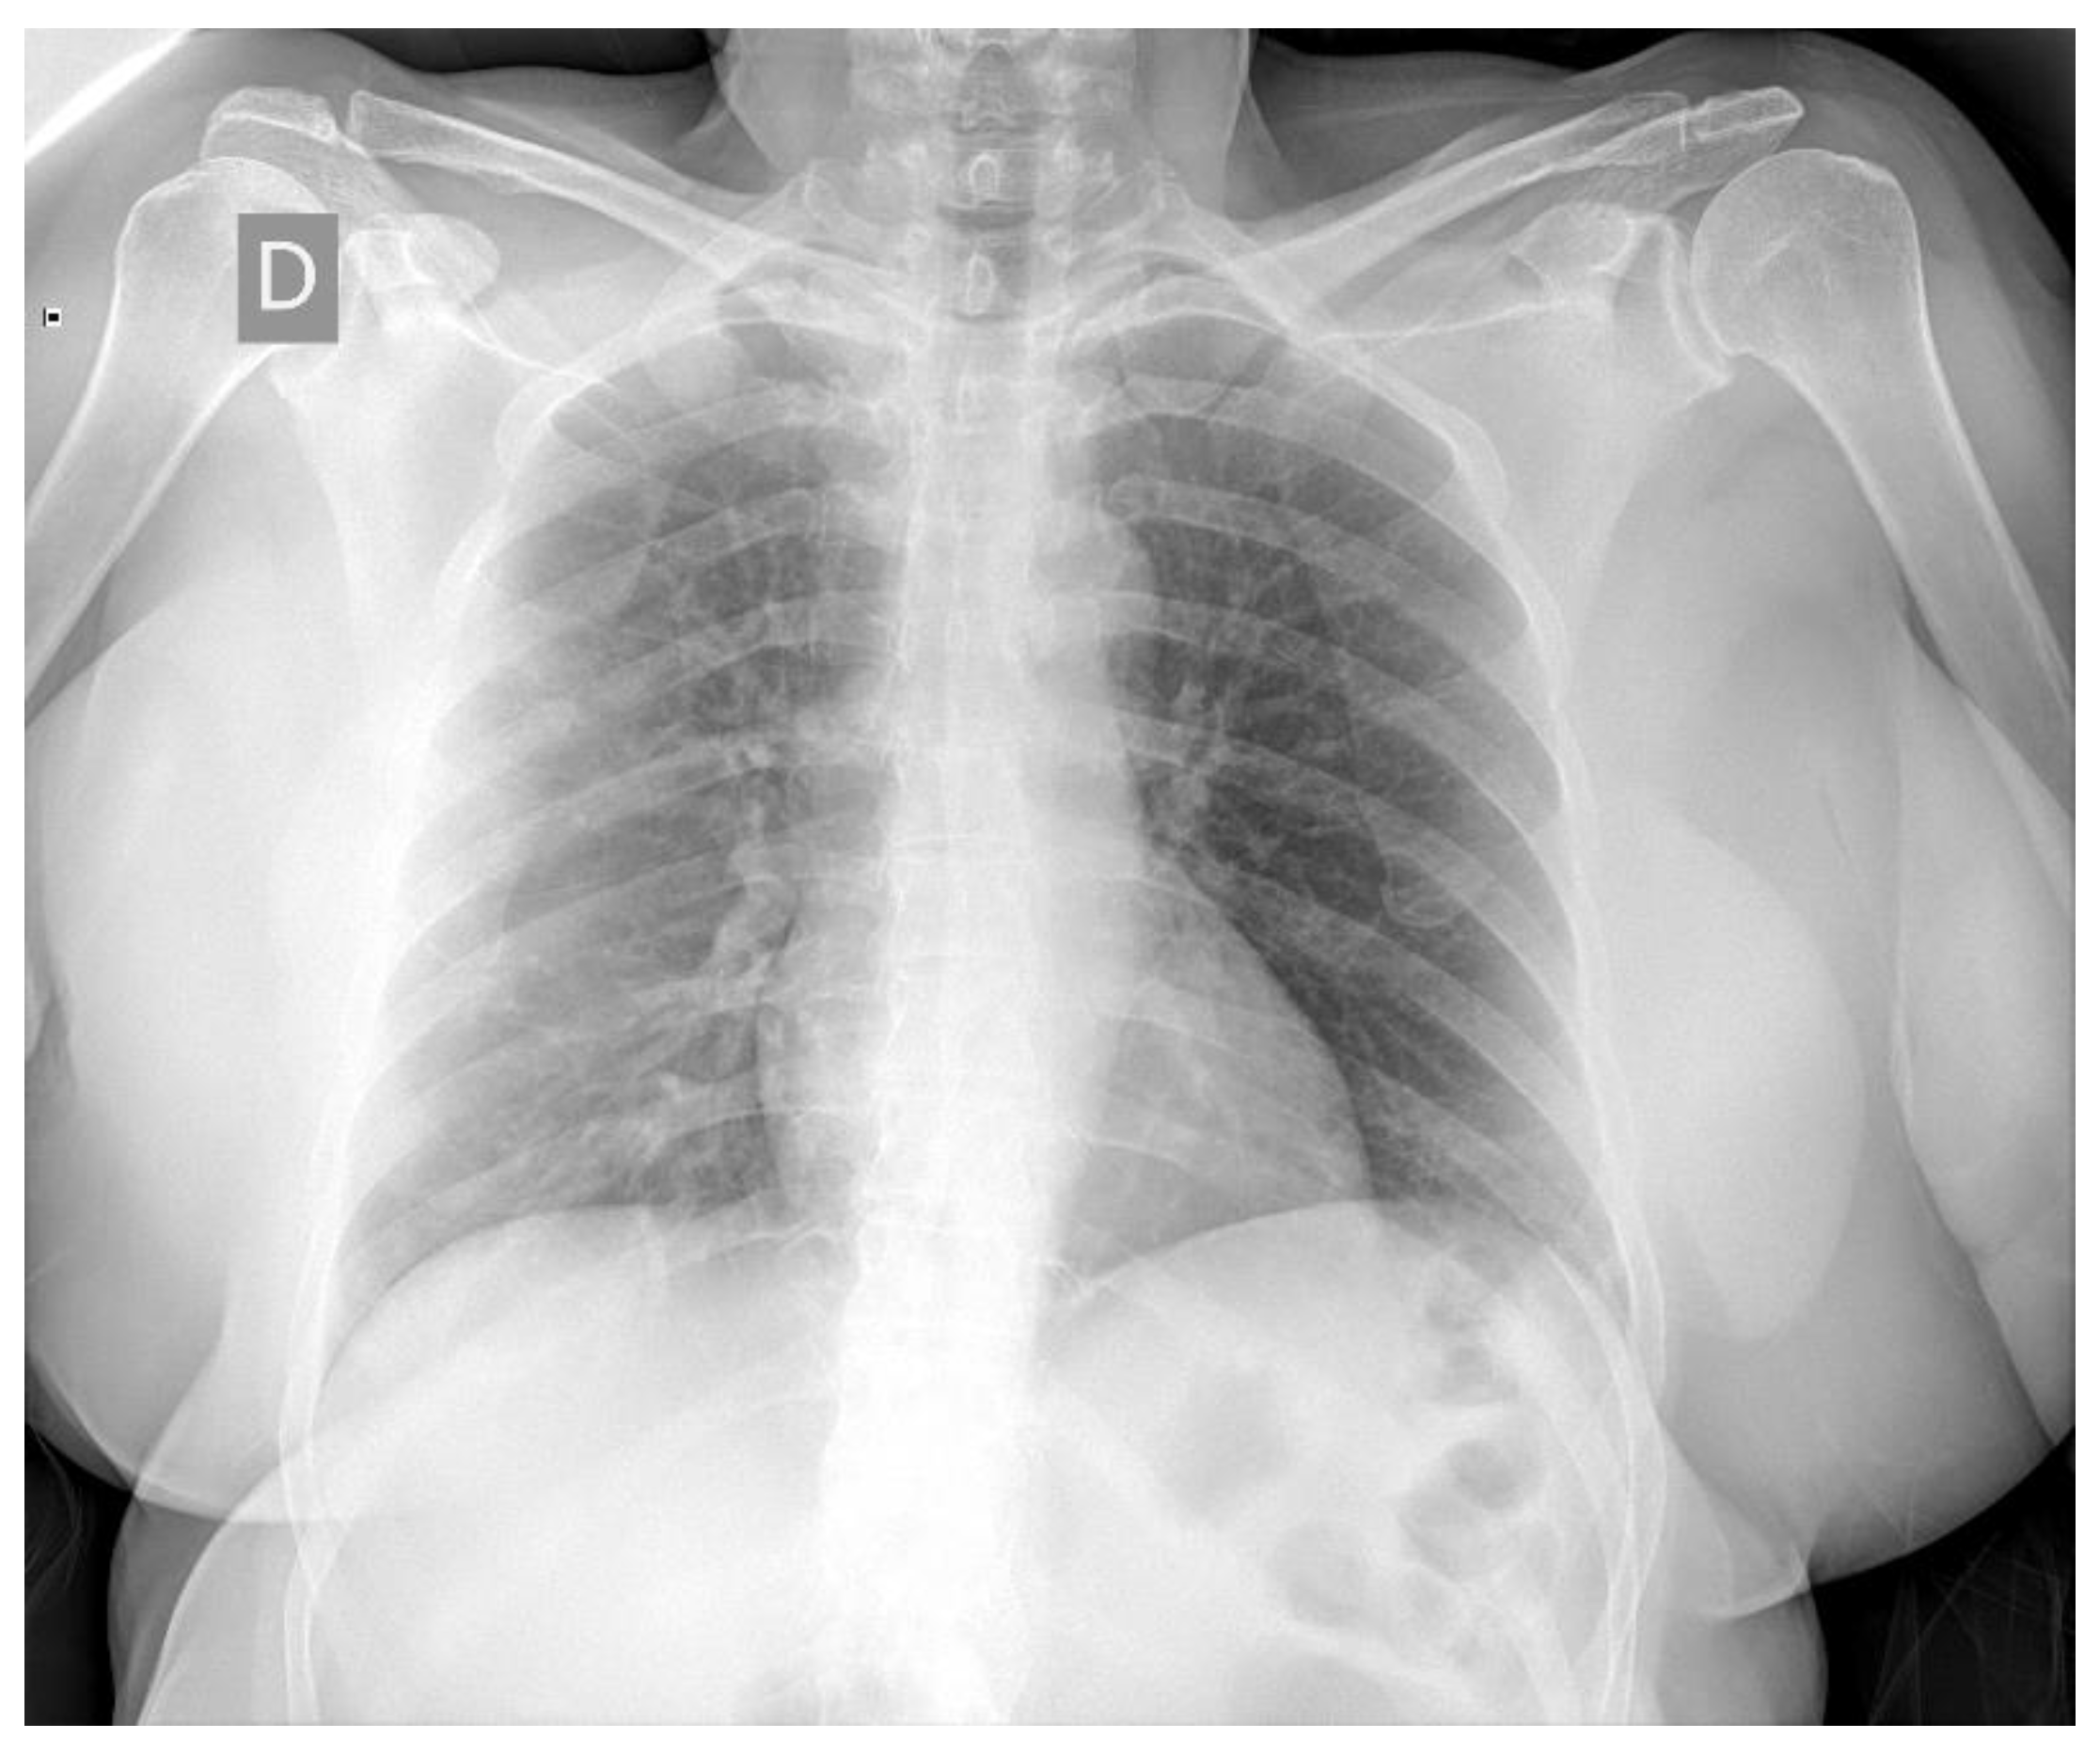

Finally, for COVID-19 cases, we used the datasets available publicly at [49,50]. The dataset presented in [49] was curated by Dr. Joseph Cohen, a postdoctoral fellow at the University of Montreal and contained images marked as COVID-19 by radiologists. We solely utilized the 239 chest radiographs in frontal angle that had been marked as COVID-19 from this dataset. Note that the dataset used for this paper was downloaded on 16 May 2020 and the images are frequently being updated so the quantity of images might differ. Figure 5 presents an example marked as COVID-19 by radiologists from this dataset. In [50], a large dataset was introduced from the Valencian Region Medical ImageBank (BIMCV) containing chest radiographs of COVID-19 patients marked by expert readers. This dataset contained radiological findings and location, pathologies, radiological reports, and DICOM metadata for 2265 chest radiographs belonging to 1311 patients. To the best of our knowledge, this is the largest COVID-19 dataset of chest radiographs available publicly. However, note that there are no normal cases in this dataset. We considered all the images in the BIMCV dataset as COVID-19, as reported in the paper associated with the dataset [50]. All studies of patients in the dataset had at least one positive RT-PCR test. Figure 6 presents an example marked as COVID-19 by radiologists from this dataset. Note that we utilized all of the datasets except BIMCV for 10-fold cross validation purposes. We conducted a sensitivity analysis experiment using the BIMCV COVID-19 dataset. We also conducted another experiment in which we split all the datasets available in our resources for a thorough hold-out validation.

Figure 6. Chest radiograph example from the BIMCV COVID-19 dataset marked by radiologists.